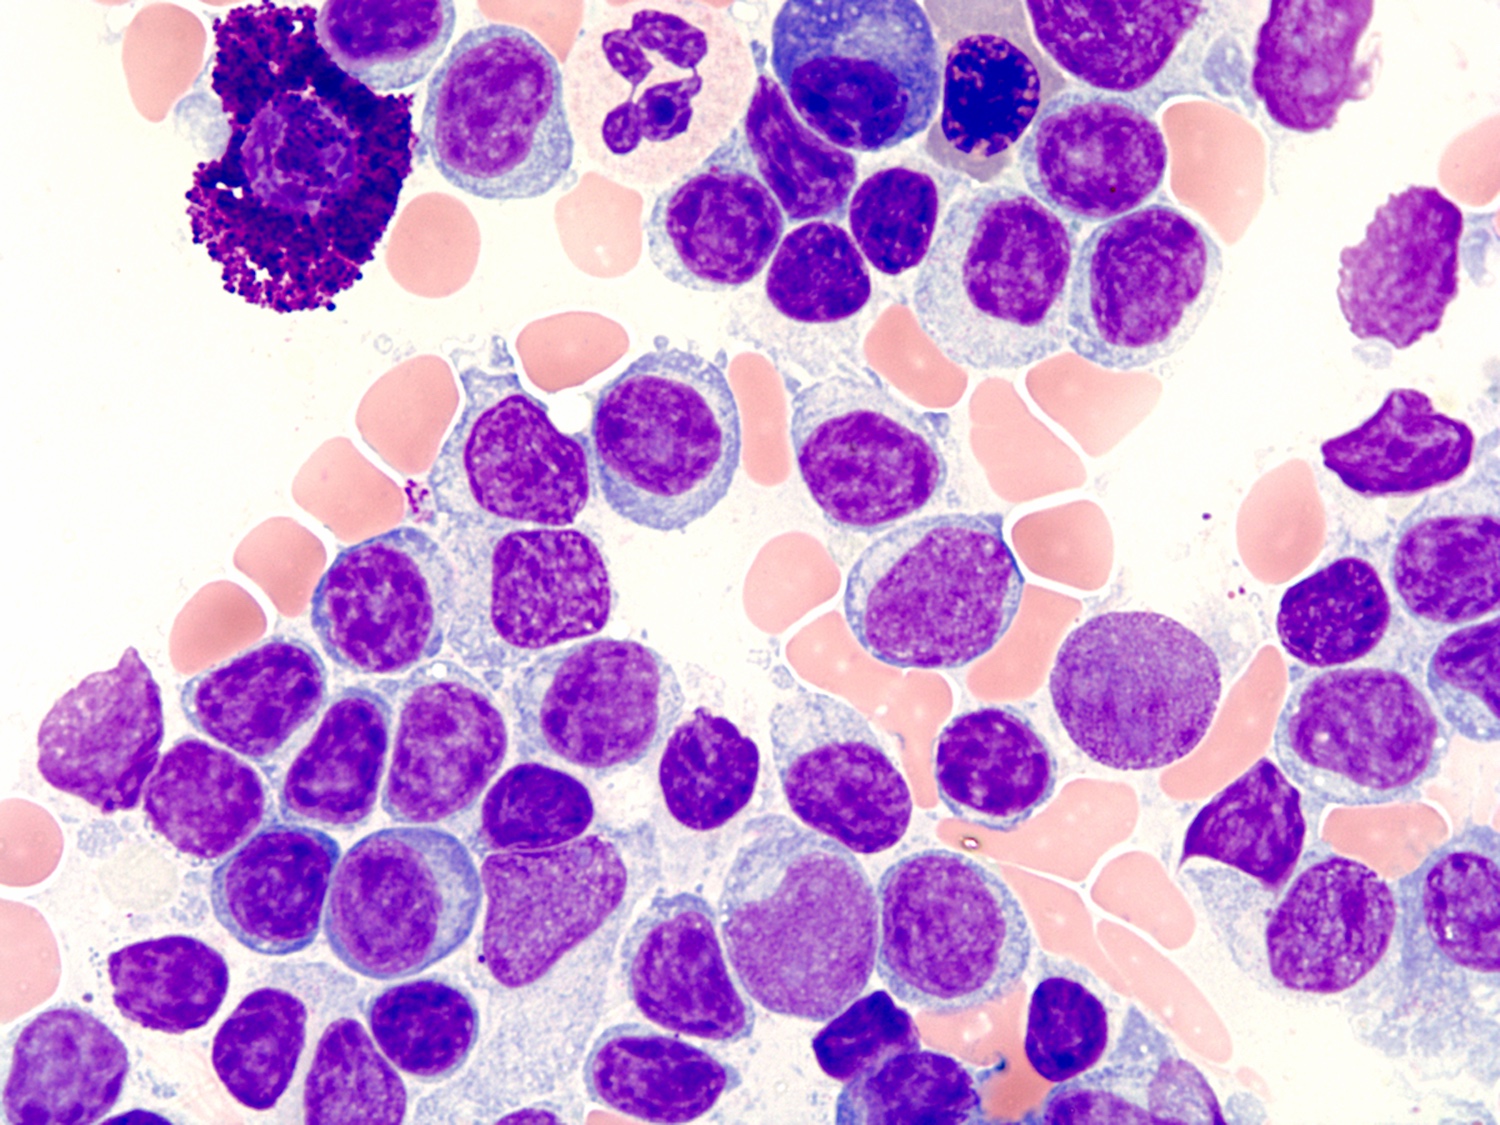

Microscopic (histologic) description

- Bone marrow (Arch Pathol Lab Med 2013;137:580)

- Aspirate is the most helpful sample in morphologic diagnosis

- Predominantly small lymphocytes with a variable number of plasmacytoid lymphocytes and plasma cells

- Mast cells are typically increased; most prominent within particles on aspirate smears

- Core biopsy (Am J Surg Pathol 2005;29:1549, Am J Clin Pathol 2015;143:797)

- Most common pattern is the combination of paratrabecular and nonparatrabecular lymphoid nodules

- Less common patterns include paratrabecular or intrasinusoidal with or without interstitial infiltrate

- Pseudointranuclear (Dutcher bodies) and intracytoplasmic inclusions (Russell bodies) are most prominent on core biopsy section

Microscopic (histologic) images

Contributed by Ling Zhang, M.D.

- Aspirate smear: The Wright stained bone marrow aspirate smears are cellular, with adequate spicules included for evaluation. Megakaryocytes are decreased in number, when identified, showing normal morphology. Myeloid and erythroid precursors show progressive maturation but are relatively decreased in number. The estimated M:E ratio is 4:1. The cellularity is composed of mostly atypical lymphocytes (84% of differential count). These atypical lymphocytes are predominantly small in size, with oval or slightly irregular nuclear contours, mature chromatin and small amount of basophilic cytoplasm. Rare atypical lymphocytes are medium in size, with plasmacytoid differentiation. Plasma cells account for 4.8% of the differential count. Scattered mature mast cells are present in the background.

- Core biopsy and cell clot: The bone marrow core biopsy includes normal appearing trabecular bone and marrow, adequate for morphologic evaluation. The marrow cellularity is very high, up to 95%. Megakaryocytes are essentially normal in number with normal morphology. Myeloid and erythroid precursors are markedly decreased in number. The marrow is diffusely infiltrated by atypical lymphocytes, accounting for approximately 80% of total cellularity, a small subset of which shows plasmacytoid differentiation. Mature plasma cells are identified. Iron stain shows adequate stainable storage iron. Reticulin stain highlights mild reticulin fibrosis. The clot section contains a few small cellular particles including predominantly atypical lymphoid cells, with findings similar to the core biopsy.